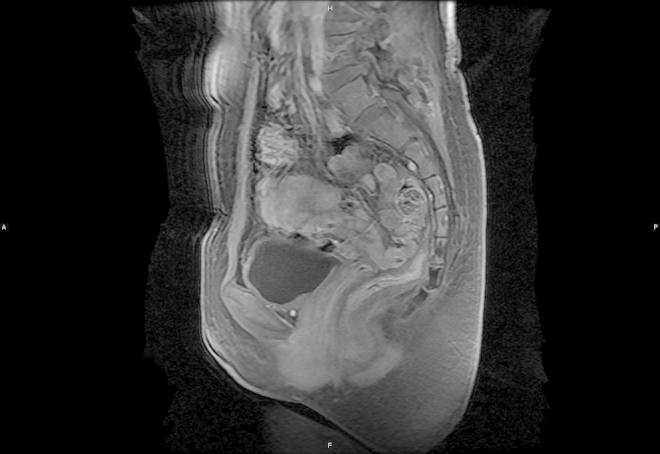

Magnetic resonance imaging (MRI) revealed the presence of a 3 × 4 × 3 cm mass which displaced the urethra laterally. The mass showed a slightly heterogenous low signal intensity on the T2-weighted images (Fig. 1). The mass displayed uniform enhancement with gadolinium administration (Fig. 2).

Figure 2.

MRI showed uniform enhancement after gadolinium administration on T2-weighed images.